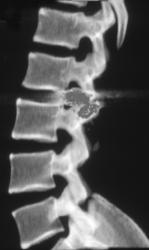

CASE NUMBER 321

Diagnosis

Humerus Fracture